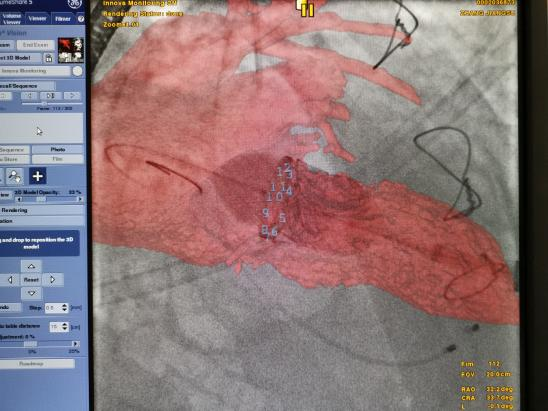

图2. 手术中虚拟融合图像进行图像融合和矫正,协助定位二尖瓣毁损瓣环透视不显影的介入瓣中瓣手术

患者李某某,72岁,二尖瓣生物瓣13年后瓣膜毁损,体质虚弱常规再次开胸手术风险很大,STS 8.4%。而且该患者生物瓣瓣环透视下完全不显影,仅能观察到三个生物瓣瓣角的点。而介入瓣中瓣技术必须要明确瓣环位置才能精准定位,调控介入瓣植入合适深度至关重要。瓣膜中心团队术中利用虚拟影像融合技术协助下,透视术野中”凭空”虚拟出来二尖瓣生物瓣瓣环,顺利完成高难度的介入瓣膜植入手术。术中超声和造影显示介入瓣膜植入深度满意,新瓣叶活动良好同时也没有瓣周漏。